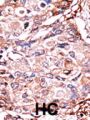

Applikationen WB, IHC-P

IHC-P: 1:50~100